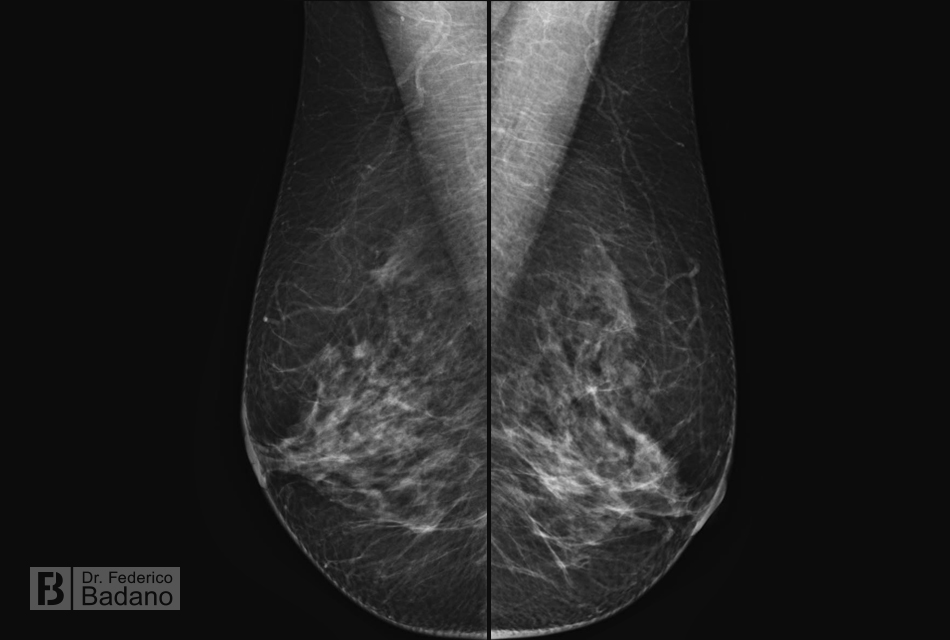

WebDiferencia entre la ecografía mamaria y las mamografías Las mamografías son la técnica que más se utiliza para detectar de forma precoz el cáncer de mama. Este tipo de. WebDiferencias entre la ecografía mamaria y la mamografía . La mamografía es la técnica de diagnóstico por imagen que utiliza rayos X. Se trata del único método.

WebLa mamografía y la ecografía de mama son exámenes diferentes y complementarios que ayudan a detectar la existencia de células cancerígenas en etapas iniciales y por esto es. WebPor su parte, la mamografía toma una imagen de la mama con rayos X, como una radiografía. A diferencia de la ecografía es un proceso un poco molesto, porque el pecho. WebLa mamografía y la ecografía mamaria son las dos técnicas de diagnóstico por imágenes más frecuentes para el estudio de las mamas. Ambos estudios se. WebLa ecotomografía mamaria es un examen complementario a la mamografía, que a través del uso de ondas sonoras ayuda en la detección precoz del cáncer de. WebEste tipo de pruebas diagnósticas suelen tener un precio elevado y la lista de espera interminable. Normalmente el precio de la mamografía oscila entre 150 y 250 euros en.

WebEn español, este estudio de rayos X de las mamas es denominado mastografía. Por otro lado, en inglés se le conoce como “mamography”, razón por la. WebExisten varias imágenes para evaluar la mama, las más comunes son la ecografía mamaria y la mamografía. Diferencias entre Mamografía y Ecografía de seno Autora: Dra.